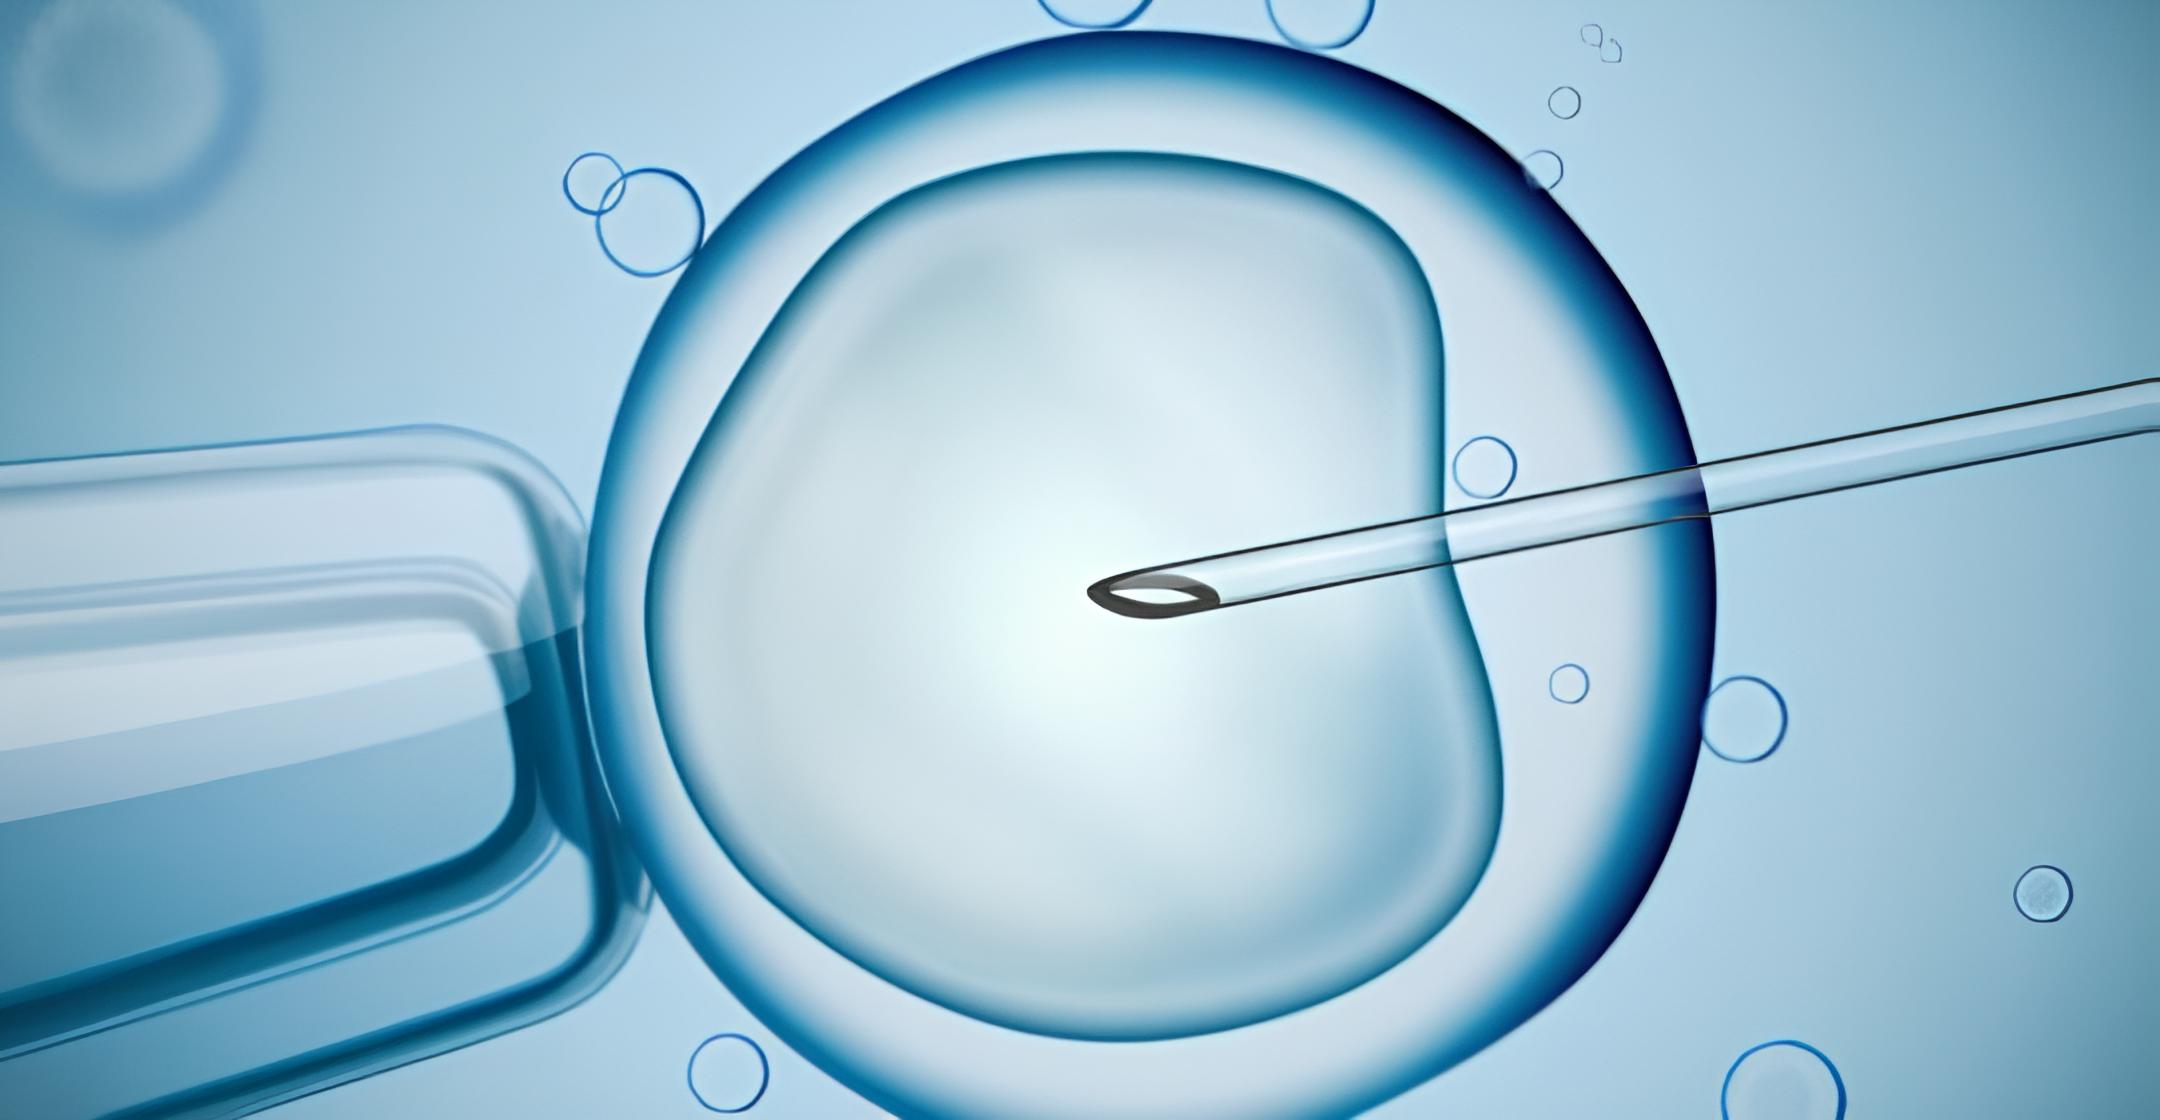

¿Por qué elegir una clínica especializada en alta complejidad reproductiva?

La búsqueda de un embarazo puede llegar a ser un proyecto largo y lleno de incertidumbre, sobre todo cuando el resultado no llega en el momento esperado. Muchas mujeres y […]